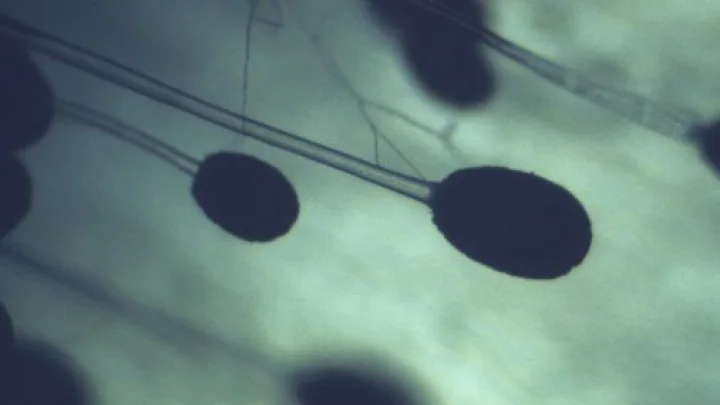

Грибы-убийцы: как изменение климата угрожает здоровью миллионов

Грибок Aspergillus может распространиться на 77% новых территорий к 2100 году.

Согласно публикации в газете Financial Times, изменение климата может привести к распространению опасного грибка Aspergillus. Из-за повышения температуры география распространения потенциально смертельных патогенов, включая устойчивые к медикаментам грибковые инфекции, может расшириться.

Учёные предупреждают о приближении "переломного момента" в распространении таких патогенов. При этом более 90% видов грибов ещё не изучены.

Аспергиллёз представляет серьёзную угрозу для людей с ослабленной иммунной системой. Ежегодно около 3,8 млн человек умирают от инвазивных грибковых инфекций.

Согласно прогнозам, если страны продолжат использовать ископаемое топливо, то к 2100 году Aspergillus может распространиться на 77% новых территорий. Это может привести к дополнительному заражению ещё 9 млн человек в европейских странах.